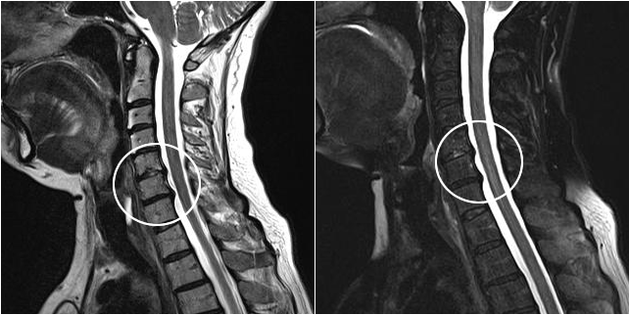

Os métodos de diagnóstico modernos inclúen resonancia magnética e TC, que permiten examinar con maior precisión os procesos de destrución da cartilaxe e do tecido óseo. Ademais, usando esta técnica é conveniente diagnosticar hernias e outros defectos dos tecidos brandos preto da orixe da enfermidade.